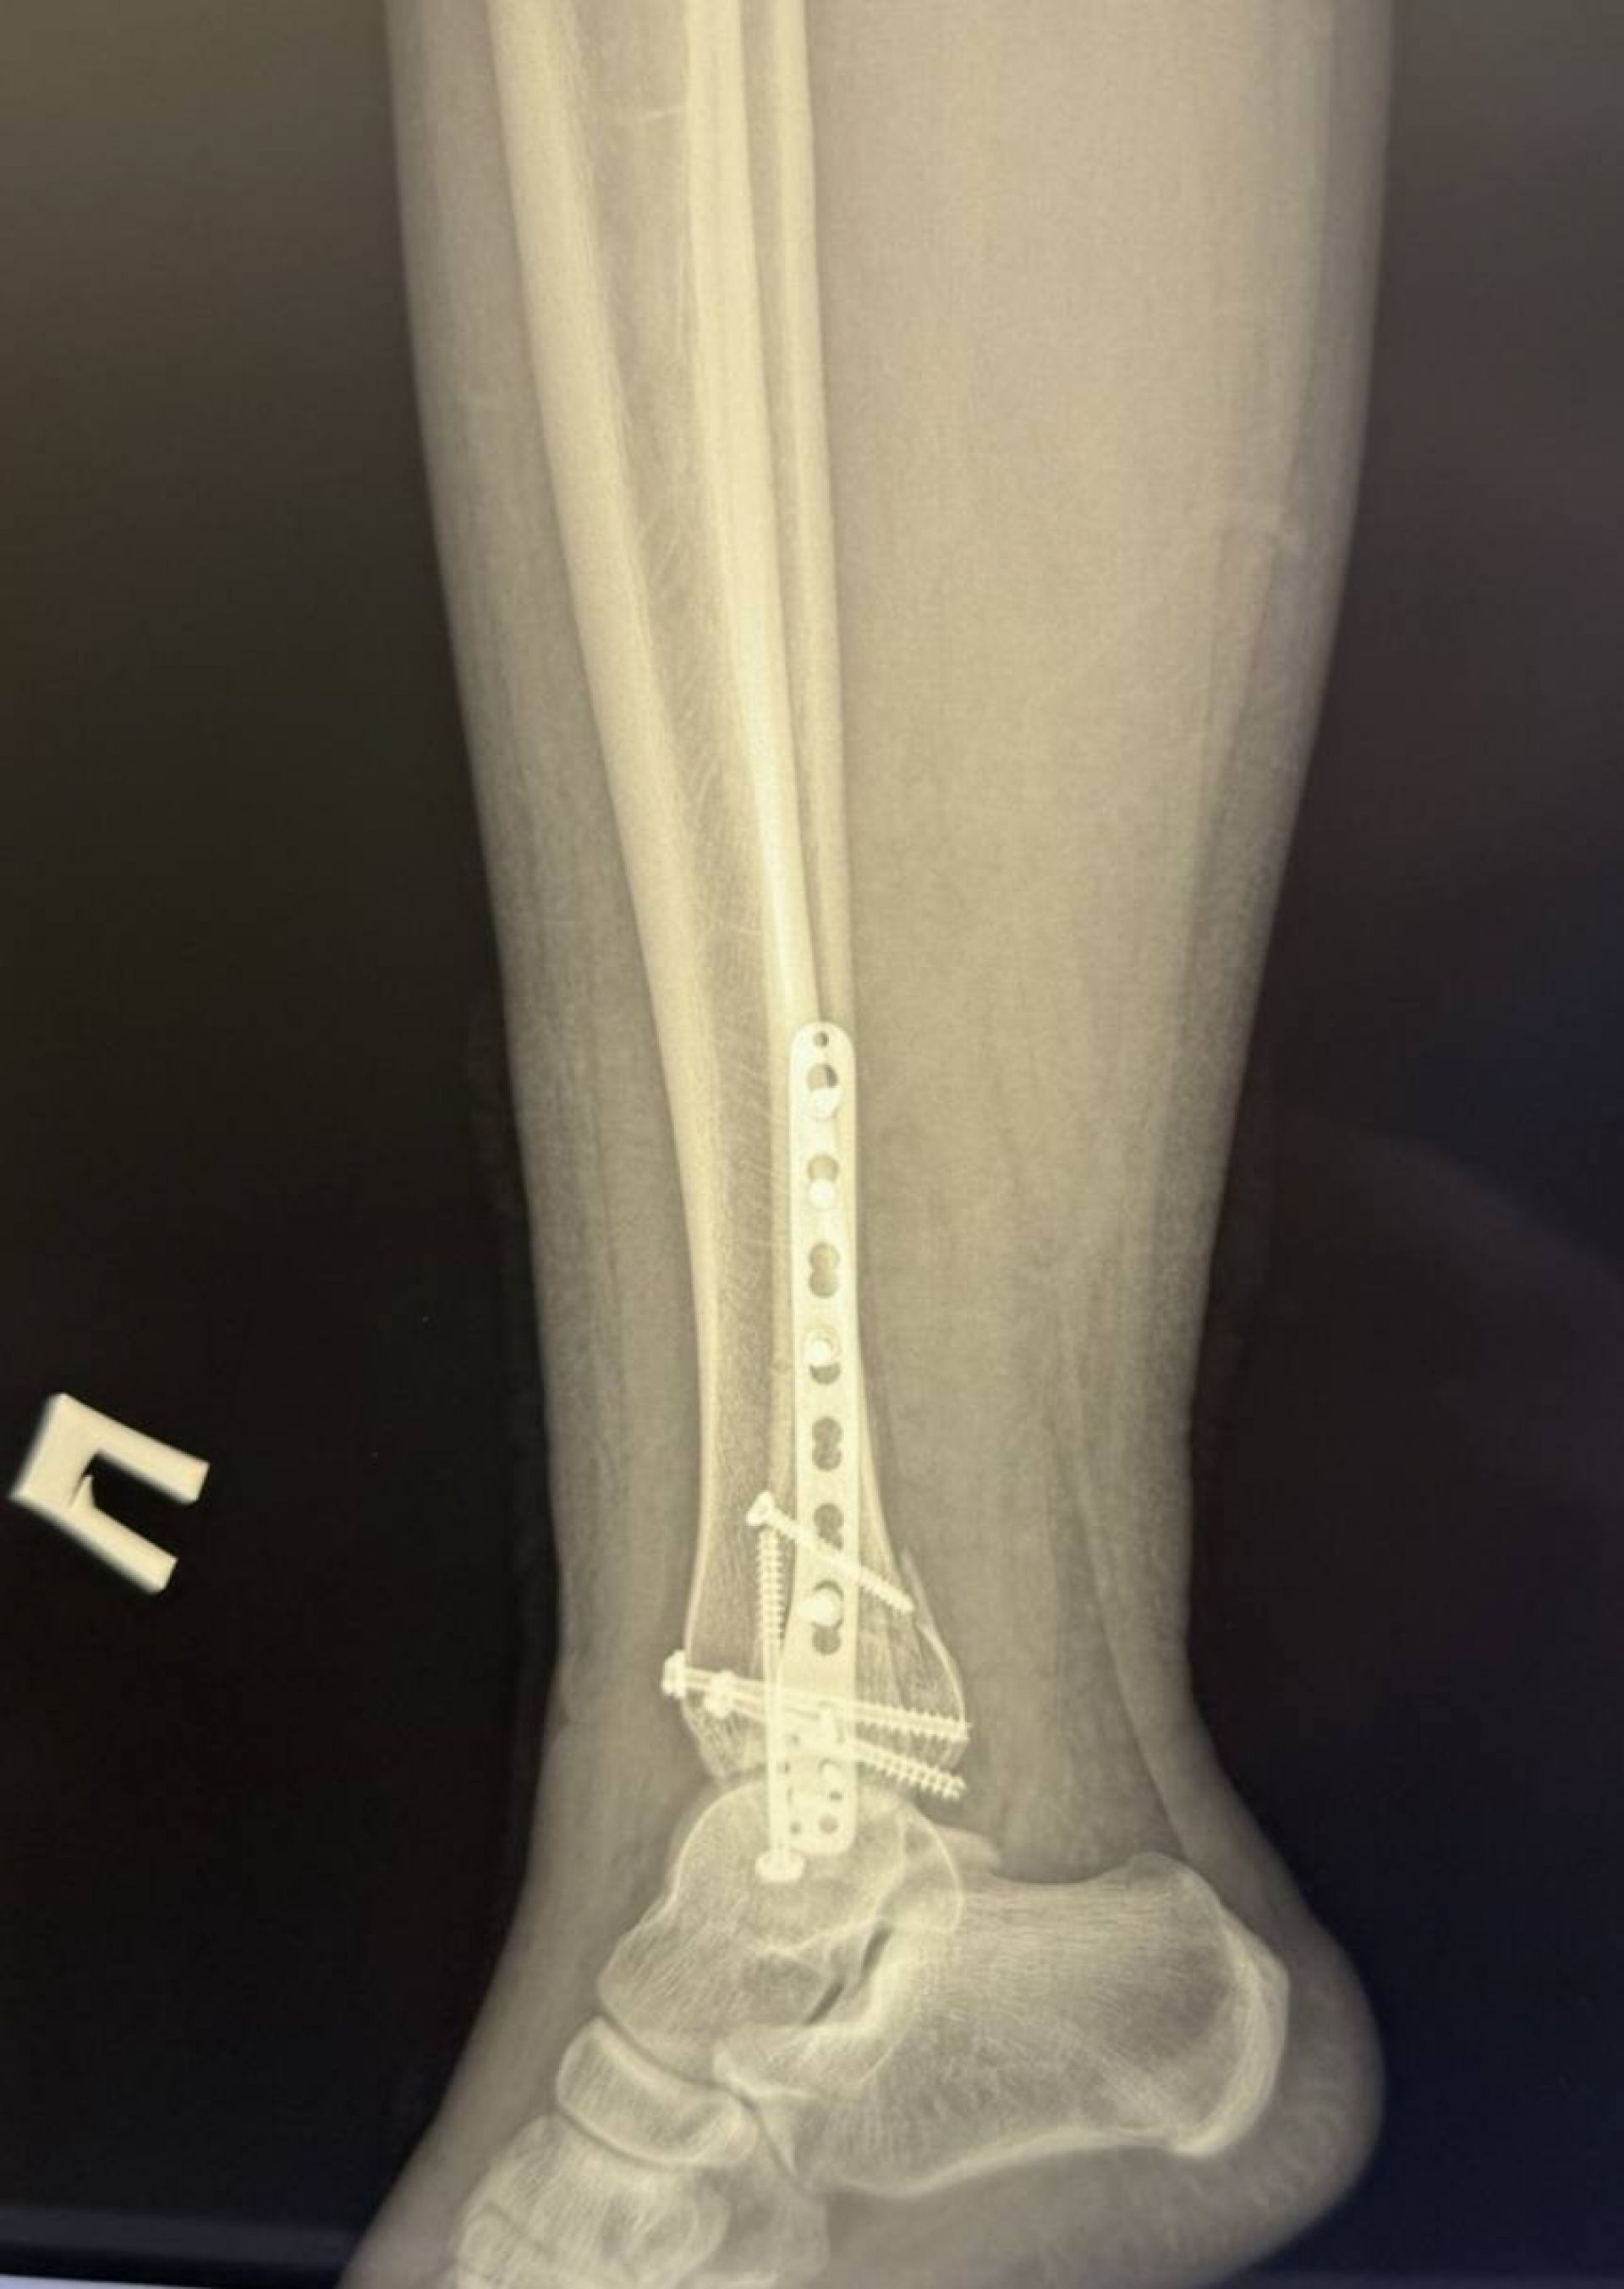

Хлопець звернувся до травмпункту, і обстеження показало, що він має не один, а цілих три складних переломи кісток гомілковостопного суглоба зі зміщенням.

Після госпіталізації та проведення додаткових обстежень (КТ) для максимально точного планування, фахівці лікарні провели складне оперативне втручання.

Головна мета операції полягала у тому, щоб зібрати всі кісткові уламки та повністю відновити стабільність суглоба. Хірурги виконали:

1. Зіставлення уламків малої гомілкової кістки та фіксацію її пластиною і гвинтами.

2. Репозицію переломів великої гомілкової кістки з фіксацією гвинтами.

3. Фіксацію суглоба спеціальним гвинтом для відновлення його стійкості.